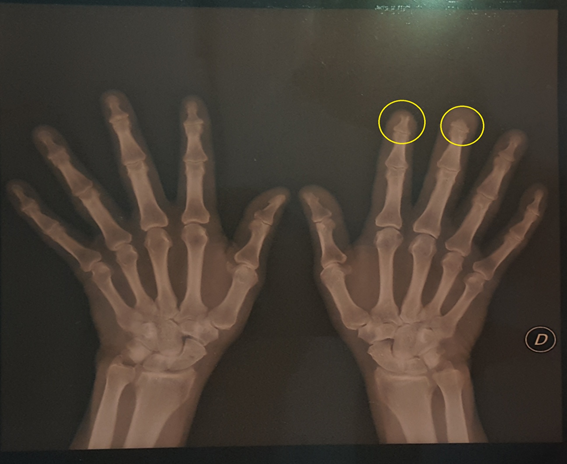

Figure 3 X-ray of the right hand where the acroosteolysis of the 2nd and third fingers is observed more closely.

Figure 4 Panoramic view of both hands where the involvement in the right hand is observed with bone resorption and loss of the distal tuft structures corresponding to the second and third fingers. There are lesions compatible with osteoarthritis and without particularities in the left hand.

One of the relevant keys in our patient was unilateral involvement, the appearance of blisters affecting the index finger of the right hand, the sclerodactyly and the loss of nail plates. On the x-ray of the hands, the acro-osteolysis of the distal phalanx of the second and third fingers of the right hand is notorious. The objective of this presentation is to highlight the importance of the suspicion of this etiology as a cause of digital ulcers; the interdisciplinary work to optimize timely treatment (which is surgery) in this type of serious and disabling pathologies.